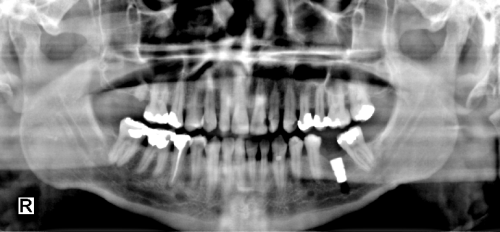

Tissue Equalize Function - After